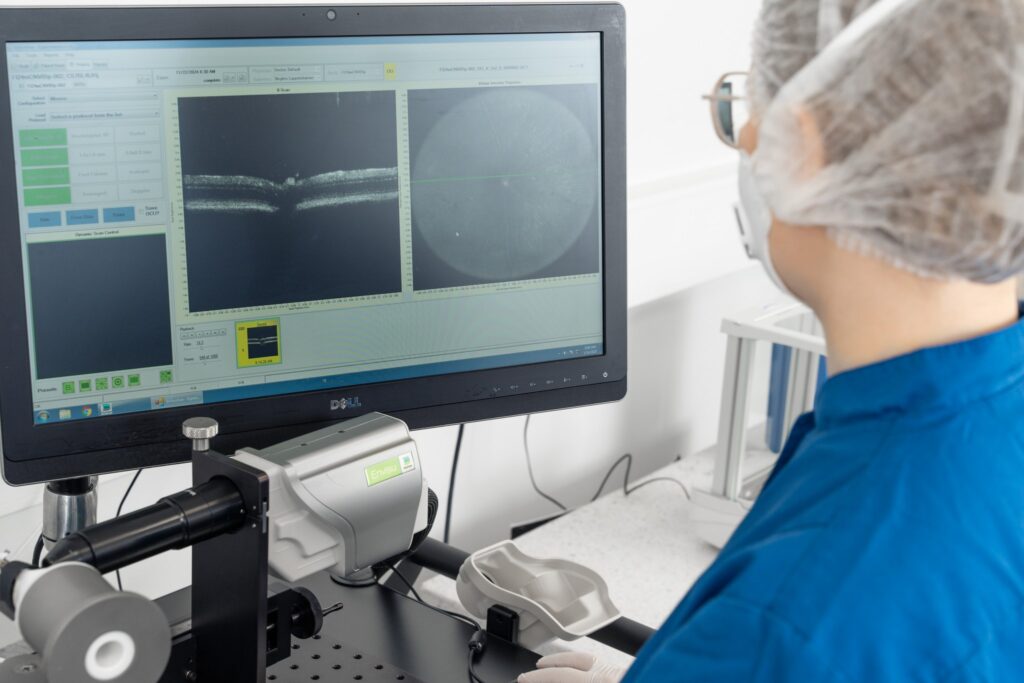

Recent advancements in in vivo imaging and electrophysiology turned this model into a powerful and validated tool for the screening of novel drug candidates with neuroprotective properties. Further innovations in AI-driven image recognition offers more precise and accurate screening of novel drug candidates.

– Inner retinal thickness measurements (SD-OCT)

Controlled IOP elevation allows adjustable severity of injury, analyzed for functional and structural insights using SD-OCT, ERG, OMR and histology.

AI-driven image analysis and stereology provide objective, reproducible RGC quantification for reliable drug efficacy assessment.